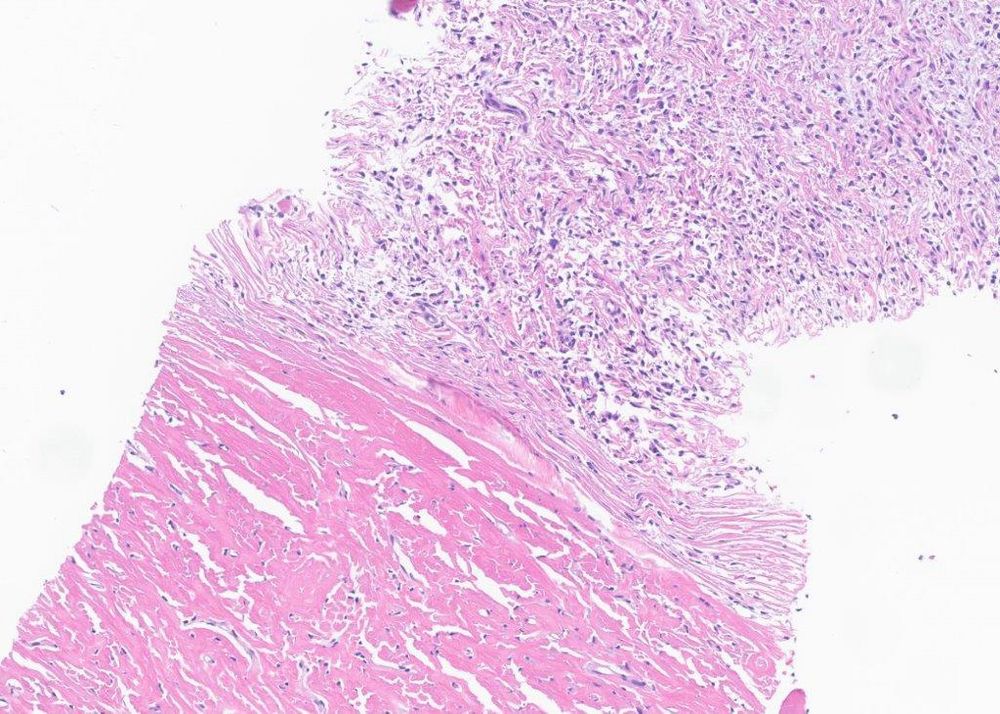

#PathSky Laryngeal mass, older adult male. Primitive, highly vascular round cell neoplasm for the most part.